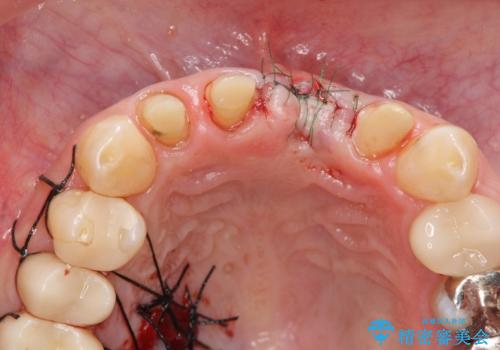

左側の前歯には他院で埋入されたポジションの悪いインプラント補綴により歯冠長の長いクラウンが装着されており、感染による排膿も認められこのまま審美性を改善するのは難しい状態です。

不良インプラントを除去し最終的にブリッジによる補綴で審美性の改善を行うこと、その準備として骨の造成・歯肉の移植による歯の欠損部顎堤のボリュームを維持・増大を計画します。

感染したインプラントからは排膿が間欠的に認められ、掻爬・除去が検討されうるような状況でした。

より審美的な改善を強く求められたため、インプラントを除去し可及的に欠損部顎堤を増大したのちブリッジによる審美改善を行いました。